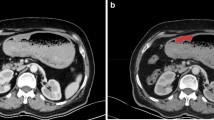

In this paper we present a set of 3D-rigid motion invariant texture features. We experimentally establish that when they are combined with mean attenuation intensity differences the new augmented features are capable of discriminating normal from abnormal liver tissue in arterial phase contrast enhanced X-ray CT–scans with high sensitivity and specificity. To extract these features CT-scans are processed in their native dimensionality. We experimentally observe that the 3D-rotational invariance of the proposed features improves the clustering of the feature vectors extracted from normal liver tissue samples.